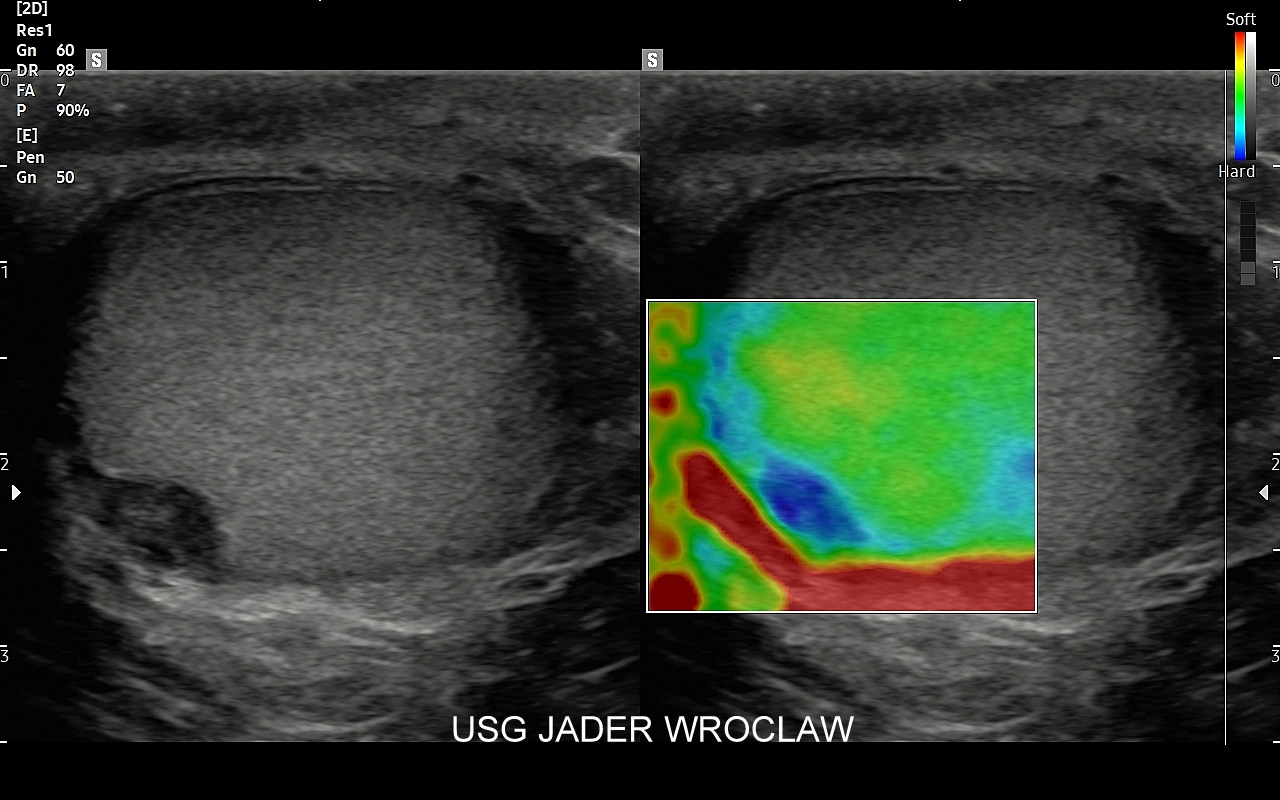

• badania Elastoscan guzów i tkanek,

Dr Tomasz Szczepański zajmuje się kompleksową opieką medyczną nad swoimi Pacjentami. W ramach Interdyscyplinarnej Pracowni USG Wrocław wykonuje szereg uzupełniających się badań, zarówno klasycznych, jak USG jamy brzusznej, USG tarczycy, USG piersi, pełen zakres diagnostyki USG Doppler, jak i wysokospecjalistycznych, w tym badania multiparametryczne (MPUS), badania USG z kontrastem (CEUS), ocena przetok dializacyjnych, badania USG Doppler przepływów nerkowych, czy badania USG twarzy